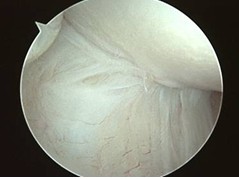

The main aim of tennis elbow surgery is to release the ECRB tendon off the lateral epicondyle. As this tendon is the deepest structure from the skin, it makes sense to approach it from the inside rather than through the skin and muscles. Elbow arthroscopy is a fast and easy way to approach the ECRB tendon from the inside of the elbow joint. It involves two tiny skin incisions at along the medial and lateral aspect of the elbow and it allows the surgeon to examine the inside of the elbow and address other pathologies such as synovitis, plica or loose bodies in addition to releasing the ECRB tendon.

Under magnification of the arthroscope, the surgeon can classify the ECRB pathologies into 3 types. Type I is a fraying of the tendon. Type II is a linear tear of the tendon. Type III is a tear of the ECRB tendon.

Using an arthroscopic shaver, the ECRB tendon can be released off the lateral epicondyle and the insertion area burred.